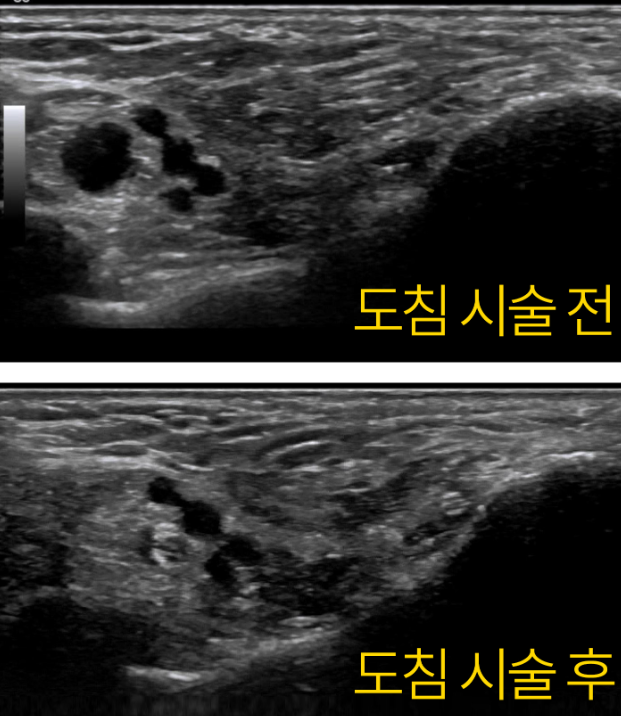

경혈 초음파로 살펴보니 거골하관절로 연결된 것이 보입니다. 예전에도 관절염으로 물이 차서 결절종을 제거했던 적이 있으셨다고요. ## 이렇게 딱딱한 물혹이 터널 안에서공간을 차지하면서 발바닥신경을 압박하고 있는데지압한다고 꾹꾹 눌러대니증상이 악화되는 것은 당연하겠죠? 더군다나 평발로 발의 아치가 무너져있는데 오래 서있으니까 도수치료, 체외충격파로도 회복하기 어려웠을 겁니다. > 초음파 유도하 도침술 발목 터널의 압력을 빠르게 해결해주는 도침 치료를 시행했습니다. 실시간 초음파로 도침을 확인하면서 신경과 혈관을 피해서 정확하게 시술합니다.

초음파 유도하 도침 시술 후에

촬영한 대종혈의 초음파 영상입니다.

결절종이 흡수되면서

내측족저신경의 경계가 선명해진 것이 보이시죠?